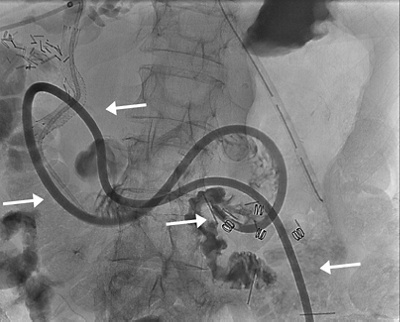

Radiologische Ernährungssonde, die von aussen direkt in den Magen gelegt wurde und im Dünndarm endet (Pfeile).